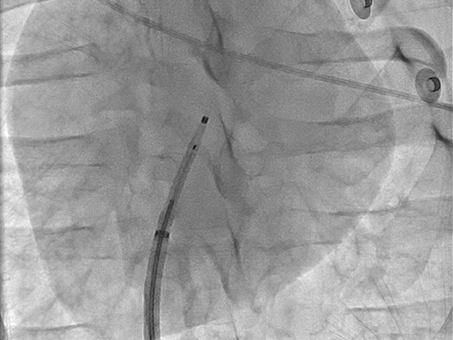

VersaCross Access Solution under fluoroscopy.

Radiopaque

The VersaCross Wire and Dilator are radiopaque so you can visualize your entire solution on fluoroscopy.